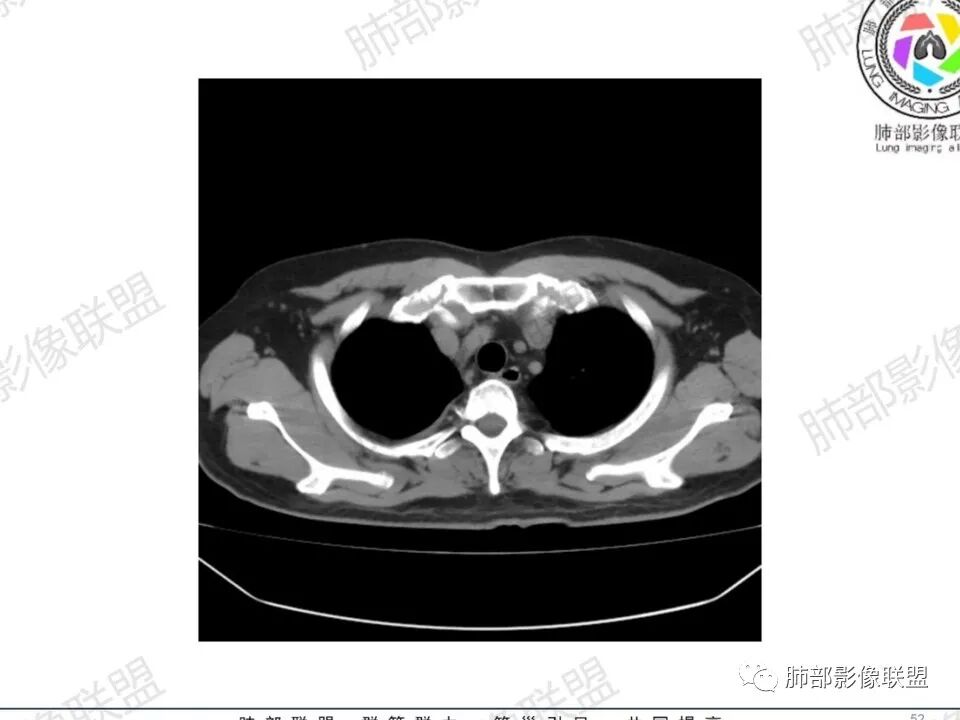

双肺多发结节,胸膜下为主,部分可见空洞。左肺上叶尖后段结节较大,分叶毛刺,周围可见长条索及小斑片影,内空洞比较光滑,内侧壁可见支气管通过。右肺下叶后基底段不张实变,后侧积液,右侧水平裂积液,右侧膈胸膜纵膈胸膜增厚积液,右侧侧胸膜肥厚,考虑1:一元金葡。2二元:金葡,左肺上叶结核。

男,45岁,左手指红肿疼痛两天,右侧胸壁疼痛伴发热12小时入院。患者急性起病,胸部CT示双肺多发结节,部分伴空洞,空洞壁较光滑,右侧胸腔积液,考虑感染性病变,金葡菌加SPE可能

中年男性,左手中指及胸壁疼痛伴发热来诊,影像见双肺多发结节,胸膜下分布为主,部分结节可见空洞,边缘模糊。左肺上叶尖后段结节较大。右肺下叶后基底段不张实变,右侧叶间裂及右侧胸腔积液,右侧侧胸膜肥厚。考虑金葡菌感染,血播SPE。

胸膜下为主多发结节,边缘光滑

伴随楔形影,支气管壁不增厚